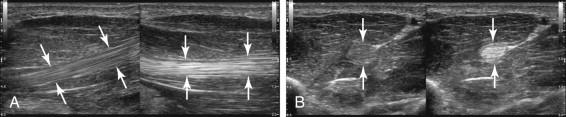

e -F igure 11-3, Tendon bow stringing due to pulley rupture. Longitudinal views of the right (A) and the left (B) flexor tendons (cursors) of the third finger show separation between the tendons and the proximal phalanx on the right side compared with the left.

Probably the most common reason for performing musculoskeletal examinations is to evaluate the tendons. Tendon tears are common and are relatively easy to identify and analyze with sonography. Complete tendon tears are associated with a number of sonographic findings ( Fig. 11-2 and Box 11-1 ). In many cases the end of the retracted proximal tendon will appear blunt on longitudinal views and will appear masslike on transverse views. It is useful to scan in the transverse plane from the intact portion of the tendon to the torn portion in order to visualize the thickened retracted end ( e-Fig. 11-1 and ). Passive or active tendon motion is also very helpful in confirming and sometimes quantifying a tear ( e-Fig. 11-2 and ). There is usually some degree of shadowing at the site of the torn proximal tendon. In most cases the shadowing is refractive in nature and does not imply underlying calcification or avulsion of bone. Another common finding is loss of the normal fibrillar architecture of the tendon or complete nonvisualization of the tendon. Fluid collections may occur at the site of torn tendons due to a hematoma (especially in the setting of a tear near or at the musculotendinous junction) or a tendon sheath effusion. Partial-thickness tears disrupt the internal fibrillar architecture in a focal region but do not cause tendon retraction ( Fig. 11-3 ).